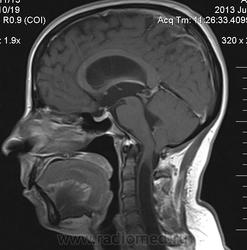

Сирингомиелия шейно-грудной локализации? Аномалия Арнольда-Киари I. Платибазия.

здоровенная сирингогидромиелитическая киста (по видимому, "высокого давления"), мальформация Киари 1.   также имеются признаки внутренней окклюзионной гидроцефалии.

Думаю, да. У человека наверняка сильно болит голова.